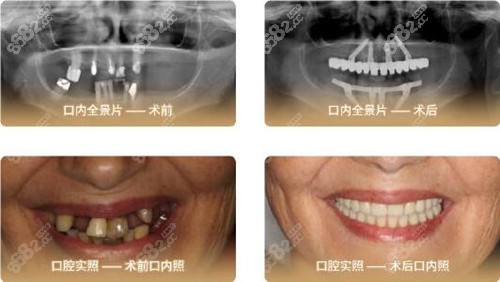

北京中诺口腔主推的立得用种植牙,和传统拍牙片上下楼奔波,检查结果等半天不同。

立得用种植牙术前检查不需要等候CT出单的过程,几分钟可完成检查,清晰的屏幕能即刻显现口腔三维立体影像,通过大屏幕了解的种植方案,在种牙前就得知道种牙后的效果。